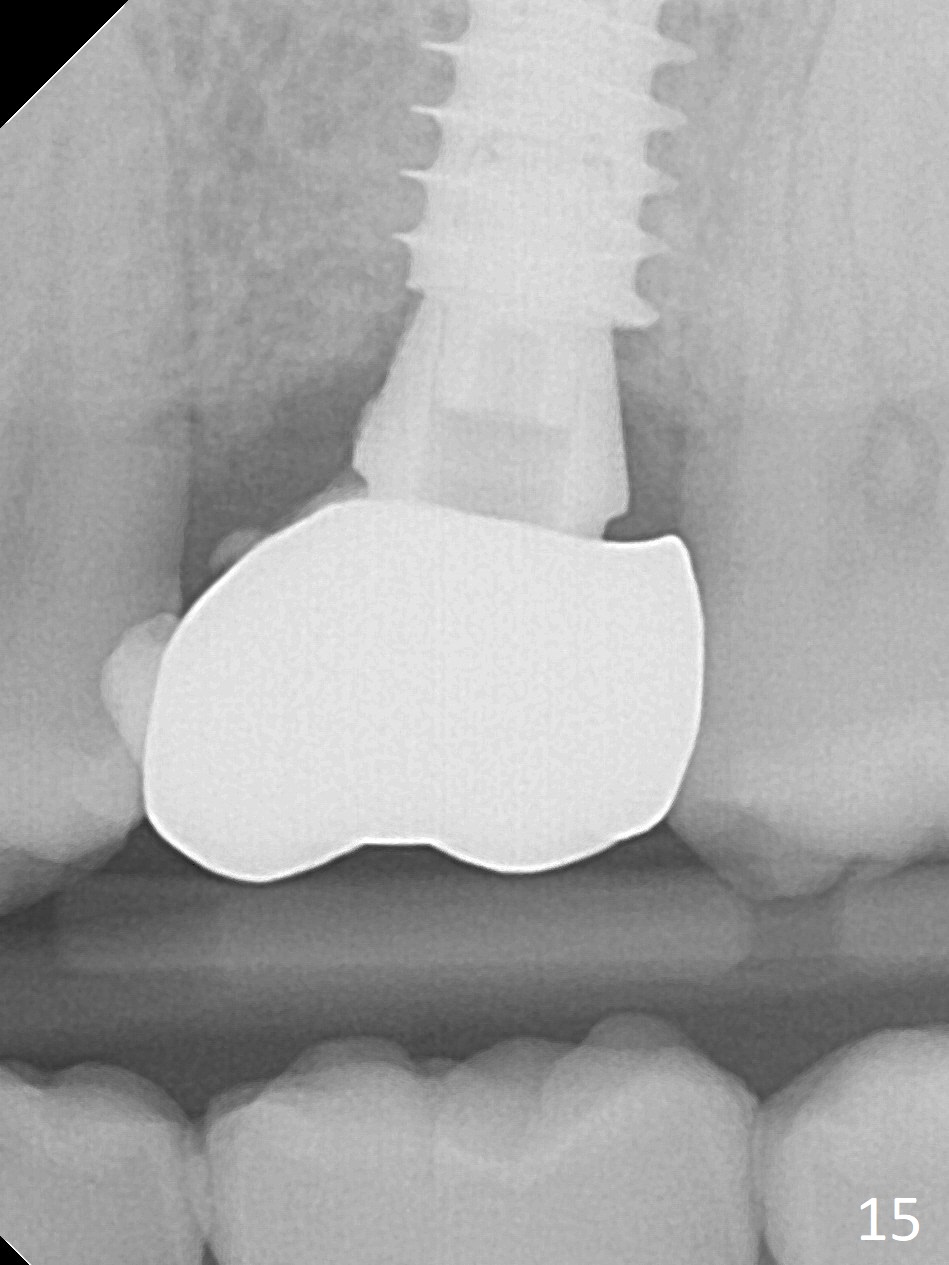

It seems that the provisional traps food. The former has been removed by the patient by the time she returns 3.5 months postop. The gingiva around the implant is healthy. The organization of the bone graft has changed (Fig.13, as compared to Fig.8,9). The implant has osteointegrated. Take photos to show the buccal and palatal gingival margin before impression. In fact the newly formed gingiva covers the margin of the abutment 5 months postop (Fig.14). Laser gingivectomy is performed prior to impression. Provisional should be kept in place with good oral hygiene. The crown dislodges 8 months post cementation, probably due to bruxism, small, short abutment and open margin (Fig.15 (taken after recementation; the residual cement is removed later)).